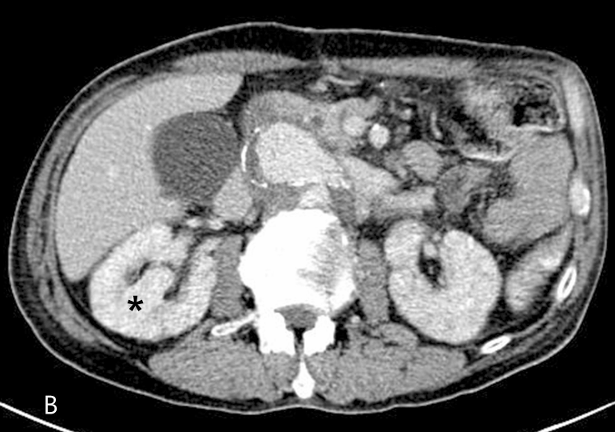

Fig 1B

Axial CT scan (B) showed luminal narrowing of true lumen (white arrow) due to the compression of false lumen (F) and stenosis of bilateral renal arteries, which were more severe in right side (arrowheads). Decreased perfusion of right renal parenchyma (asterisk) was also noted.